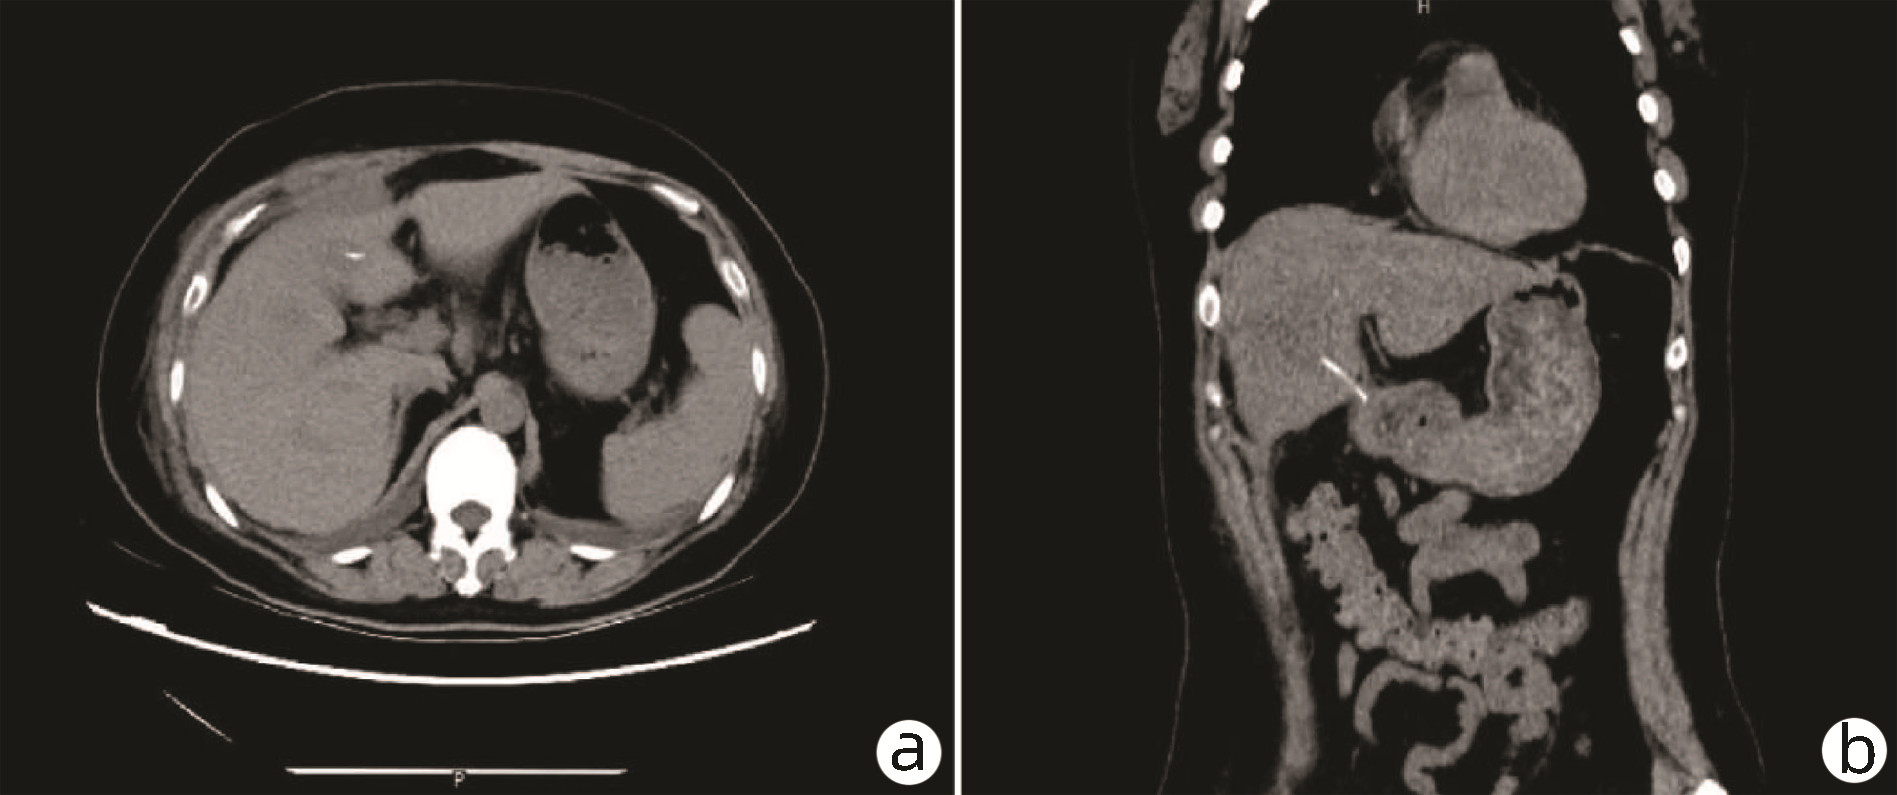

巨大肝血管瘤伴弥漫性动脉-门静脉瘘1例报告

周帮健, 杨俊, 印于, 朱晓黎, 倪才方, 王万胜

2023, 39(3): 640-643. DOI: 10.3969/j.issn.1001-5256.2023.03.025

摘要(1061) HTML (229) PDF (3500KB)(116)

摘要: